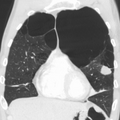

A chest X-ray is not useful to establish a diagnosis of COPD but it is of use in either excluding other conditions or including comorbidities such as pulmonary fibrosis and bronchiectasis. Characteristic signs of COPD on X-ray include hyperinflation (shown by a flattened diaphragm and an increased retrosternal air space) and lung hyperlucency.[5] A saber-sheath trachea may also be shown that is indicative of COPD.[110]

Very severe emphysema with lung cancer on the left (CT scan)